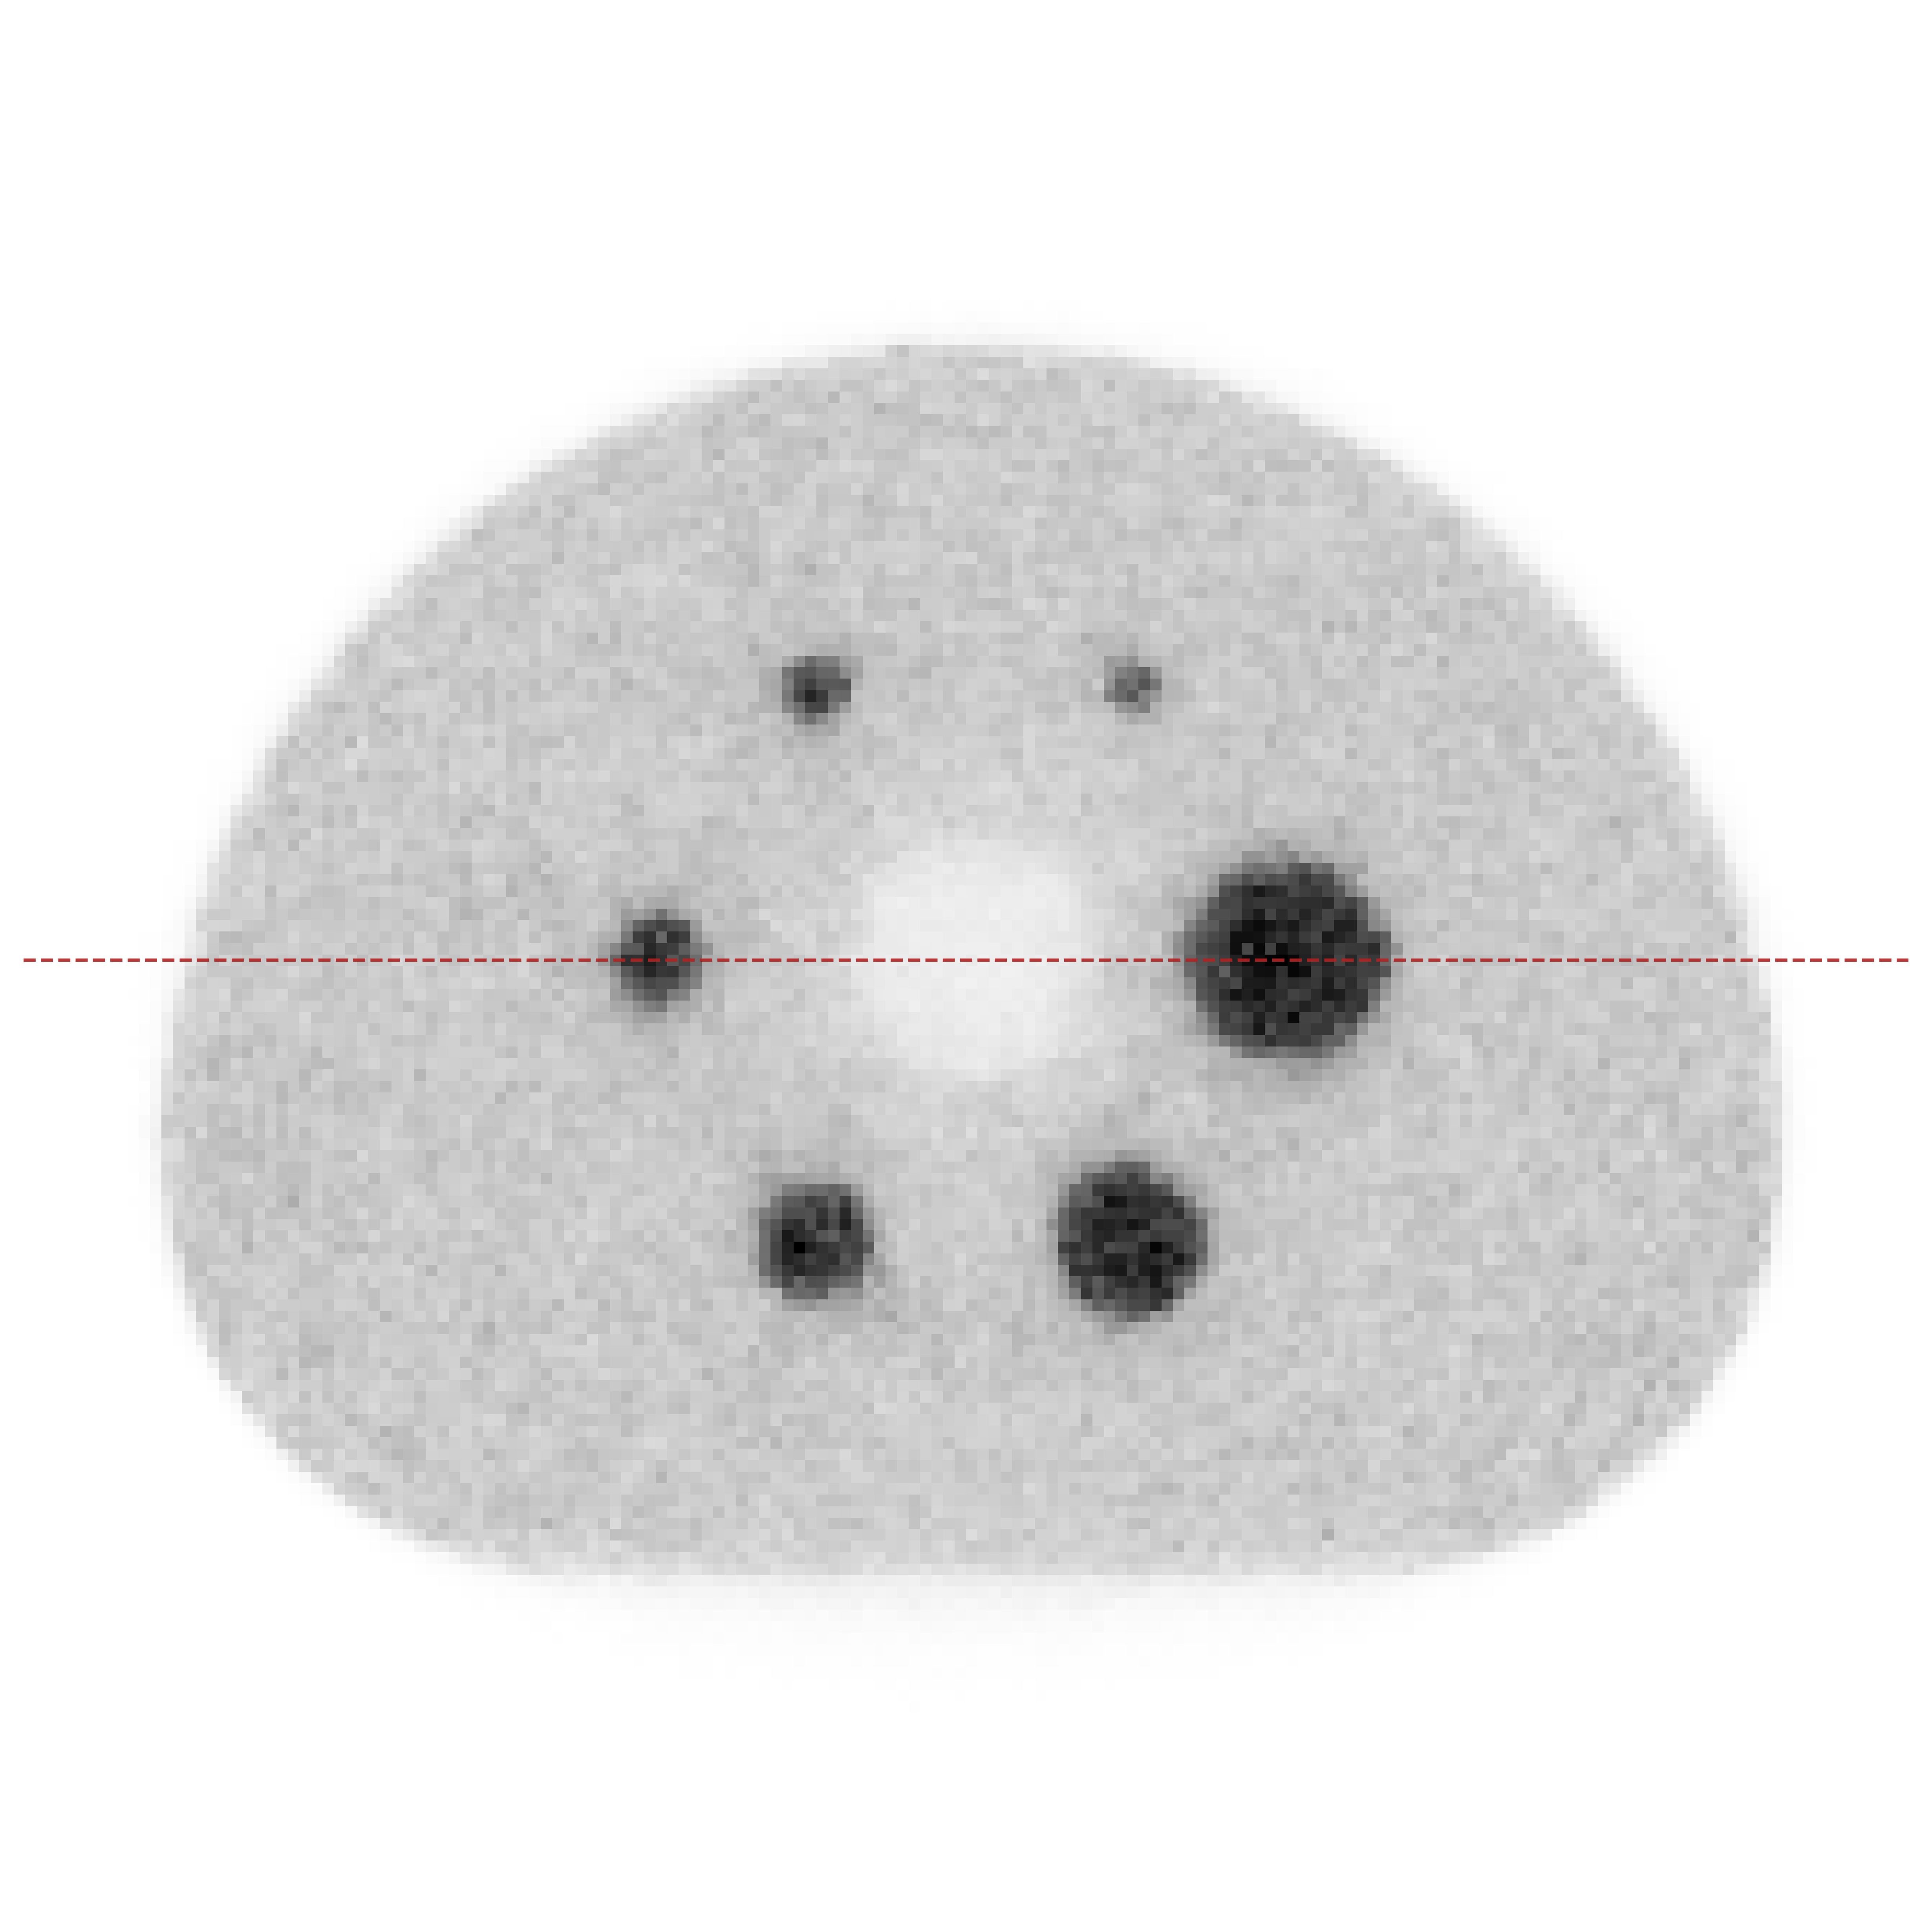

Point sources are commonly used to measure the spatial resolution of PET systems [16], since spatial resolution is typically defined as the FWHM of the Point Spread Function (PSF) [2] and is calculated from the line profile through a reconstructed image of a point source in air. The results of the three-point-source Monte Carlo simulation are shown in Fig. 5. All reconstructions were produced by our method; Fig. 5(a) and Fig. 5(b) show results without and with arc correction, respectively. Here we also measured the FWHM of the three point sources. For the non-arc case, the FWHMs are 3.43, 3.69, and 5.56 pixel, respectively. For the arc-corrected case, they are 3.45, 3.82, and 4.56 pixel, respectively. Since the three point sources were set to the same activity, their reconstructed values should be similar. The arc-corrected reconstruction yields values that are closer to each other. The results show that applying arc correction can improve spatial resolution and quantitative accuracy [9, 19], especially for sources far from the center of field of view.